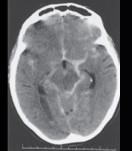

问题 男性,23岁,突发剧烈头痛5小时入院,行头颅CT出现如图所示病变,应诊断为 ( )

选项 A、硬膜下出血 B、硬膜外出血 C、脑梗死 D、蛛网膜下隙出血 E、脑出血 一、单项选择题

答案 D